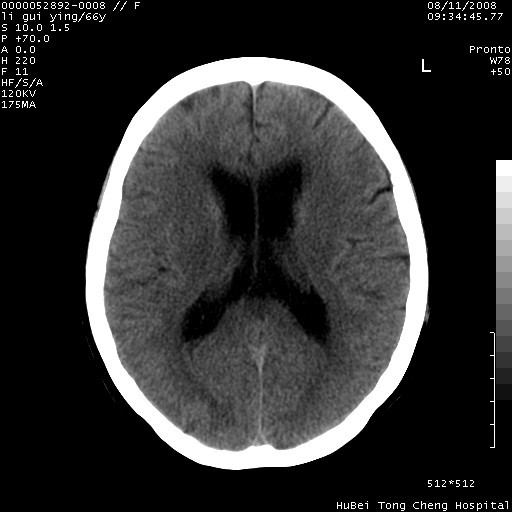

以下是引用yangyudong333在2008-8-12 12:22:00的发言:[br]1.病灶呈圆形[br]2.周围无水肿带[br]3.密度不均匀,内有点状钙化[br]4.无占位效应[br] 考虑良性占位性病变,血管瘤可能性大